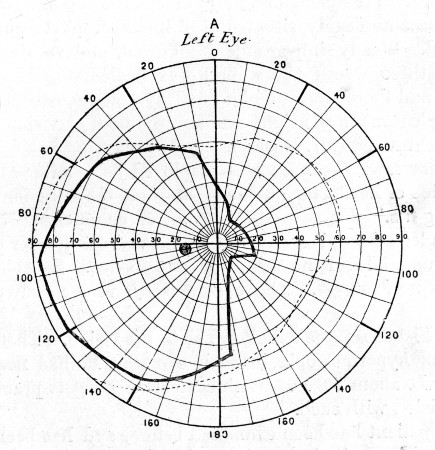

74. " " " 279

75. " " " 281